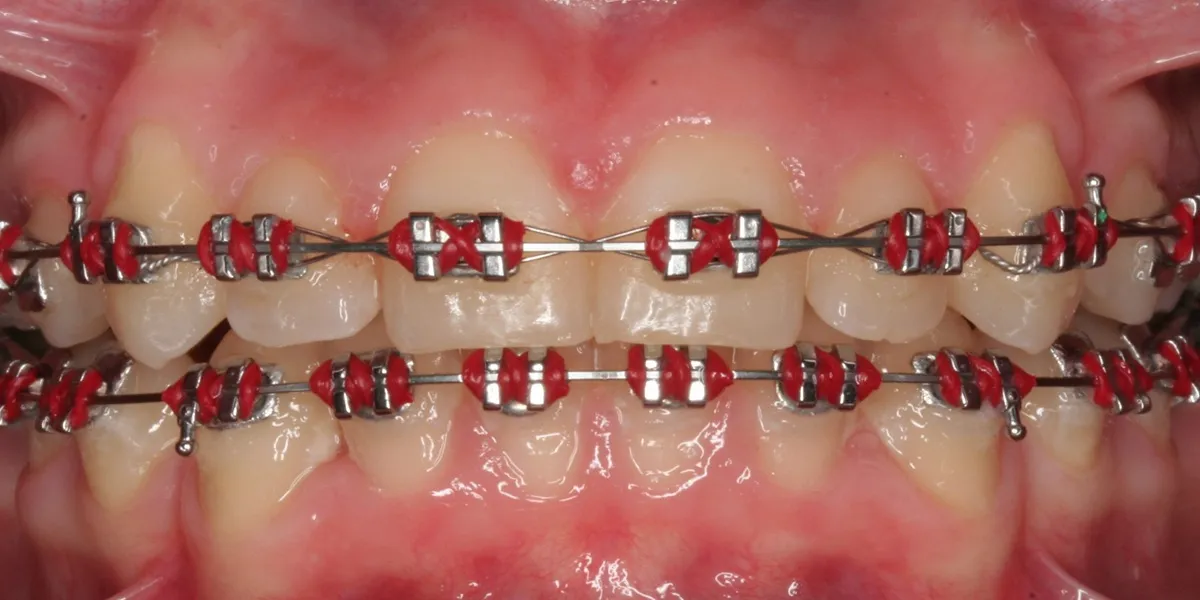

امروزه ارتودنسی دیگر تنها محدود به براکتهای فلزی سنتی نیست. با پیشرفت فناوریهای دندانپزشکی و ابزارهای نوین، روشهای جدید ارتودنسی دندان امکان اصلاح ناهنجاریهای دندانی و فکی را بدون درد و با زیبایی بیشتر فراهم کردهاند. این روشها، ضمن کاهش زمان درمان و افزایش راحتی بیمار، زیبایی لبخند را به…